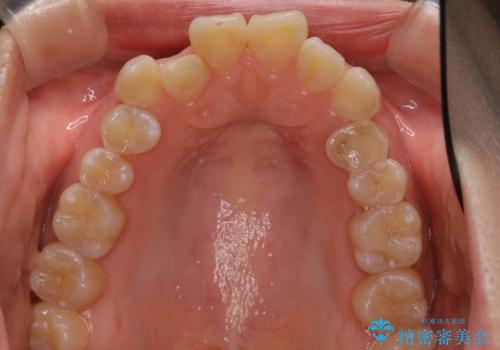

ハーフリンガル矯正 抜歯をして前歯を下げる

- 上顎の両側第1小臼歯抜歯による抜歯矯正を計画した。

上顎の抜歯により上の前歯の位置を大幅に後ろに下げることができます。

奥歯の位置関係など、様々な要素を加味し、適応を判断する必要があります。